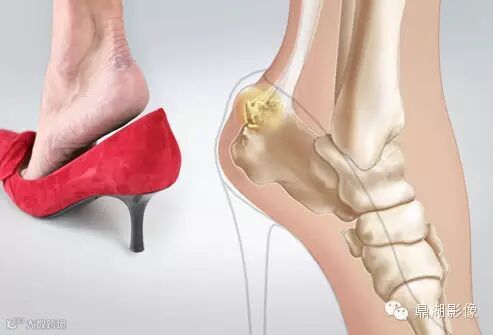

5摩擦性后跟病

Haglund 畸形(Pump bump)是由跟腱与皮肤之间不确定的浅表腱前滑囊的慢性炎症引起的。据Jones的资料,约50%的患者存在此滑囊。腱前滑囊炎通常是由于坚硬鞋后帮的慢性刺激引起的。减轻鞋的磨擦常可缓解症状。此畸形常发生于20~40岁的女性。